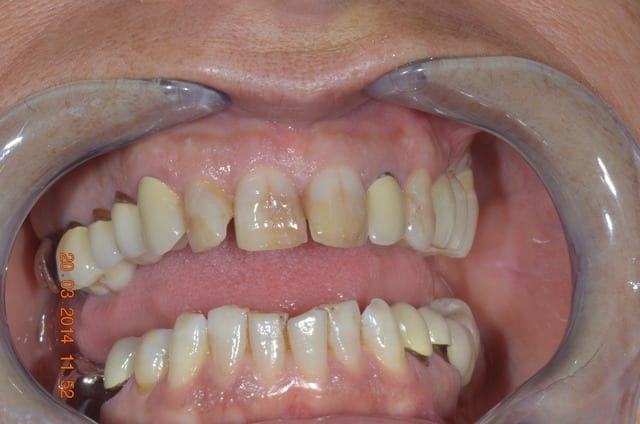

bonjour, pour des implantos exclusifs c'est surement fréquent, mais pour un omnipraticien comme moi, c'est pas tout les jours ! j'étais content en fin de traitement.